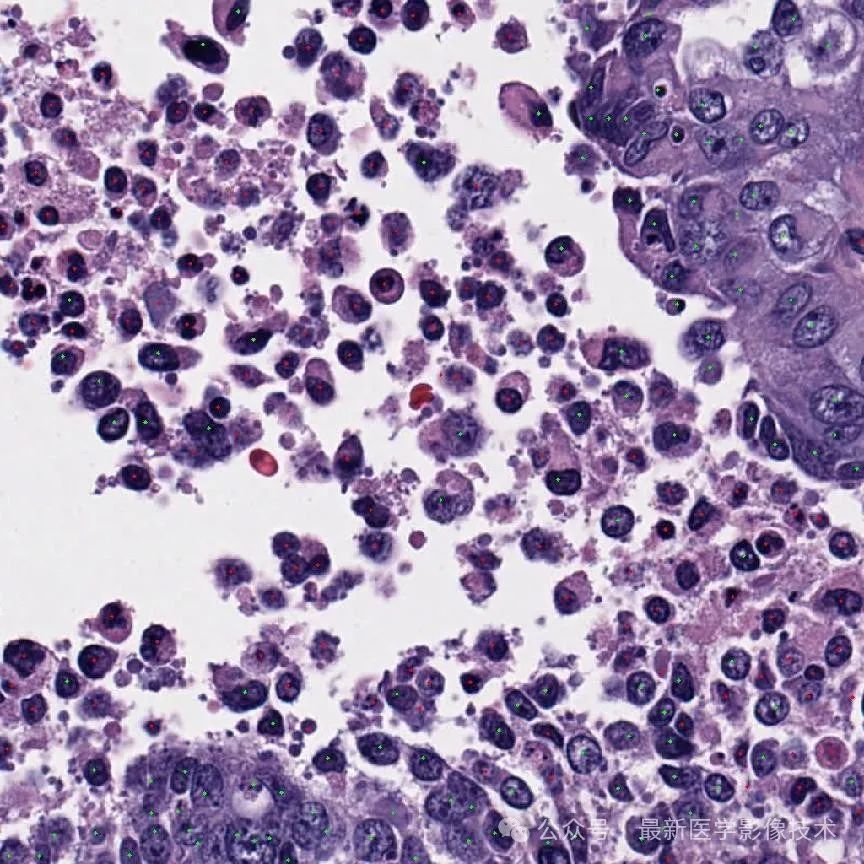

4、验证集部分检测结果

第一个是金标准结果,第二个是网络检测结果。

细胞检测结果